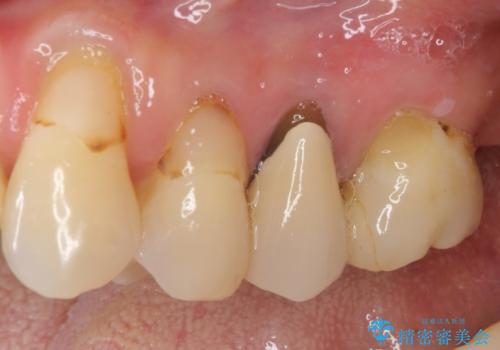

- 歯肉が退縮したためにクラウンの縁や歯根が見えてしまっていることを気にして来院された患者様です。

仮歯に変えた後にオールセラミッククラウンにて補綴することとしました。

強い咬合力や磨きすぎなどにより、歯根が見えてしまったり、金属の縁が見えてしまったりし、審美障害を引き起こすことがあります。

歯根が変色してしまうと、歯肉越しに歯根の黒い色が透けてしまうことがあり、この点についてはどうにも施しようがないため、患者様には事前のご理解いただきました。